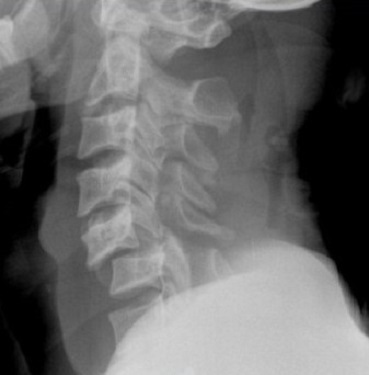

L'arthrose cervicale consite en une "usure" des articulations. Des excroissances osseuses appelées "ostéophytes" peuvent apparaitre. S'ils sont trop développés, ils peuvent rétrécir le diamètre du canal et de foramens, comprimant des racines nerveuses ou la moelle epinière. Des symptômes douloureux sont ressenti dans les épaules, bras ou mains. On parle alors de névralgies cervico-brachiales.

La discopathie est le terme utilisé pour qualifier un disque intervertébral "usé". Les disques s'altérent avec le temps, ils se "déshydratent" et perdent une partie de leurs propriétés mécaniques. Dans certains cas, cette dégradation est sévère ou rapide, sur un ou plusieurs niveaux, pouvant entrainer des douleurs cervicales.

La colonne cervicale est sujette à des lésions osseuses ou ligamentaire suite à un choc (chute, accident de voiture...). Ces lésions peuvent parfois être méconnues initialement. Une déformation ou une instabilité de la colonne cervicale peuvent s'associer à des douleurs cervicales.